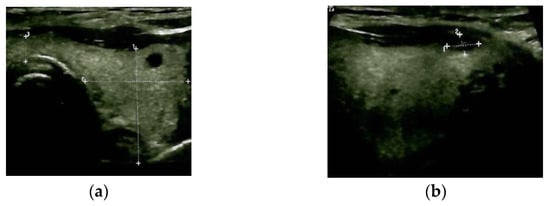

Blood exams showed mild anaemia in addition to normal thyroid function and negative thyroid antibodies. A thyroid ultrasound revealed a multinodular goitre with a hypoechoic pattern with several nodules of less than 0.6 cm; the largest nodule of 1.1 by 0.6 cm was detected at the upper part of the right thyroid lobe, with no tracheal deviation and no connection to the sternal mass (Figure 3).

Figure 3.

Thyroid ultrasound: multinodular goitre with hypoechoic pattern (a): transverse plane; (b) (right) sagittal plane.